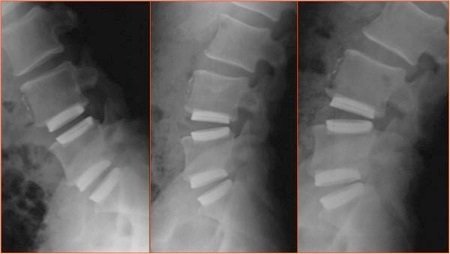

Spine cages are implants for levelling and relieving the pressure on the spine. These implants are minimally invasive normally used in conjunction with screws made of Titanium in patients with problems caused spinal instability stenosis or many others spinal degenerative diseases. The cages themselves are made of PEEK (polyetheretherketone), a highly biocompatible material, even for allergy sufferers. In the past, these cages were manufactured conventionally in titanium, with the result being that, in some cases, the titanium component had a negative impact on the bone structure due to the rigidity of the cage realized by drilling with a very hard structure. This was caused by the implant's significantly lower elasticity versus the bone. One alternative is PEEK, a high-performance plastic with compression properties or elasticity (E-module) rivalling that of bone. In addition, PEEK components cause no artefacts in MRI (magnetic resonance imaging) and are thus easy to locate by the surgeon through imaging. One of the disadvantages of PEEK spine cages is their inability to be integrated into the bone structure and their eventual should slip off from the original position also after longer periods of implant. Polyetheretherketone is a high temperature resistant thermoplastic and belongs to the group of polyaryletherketones. Its melting temperature is 335°C.

The LaserCUSING additive laser melting method combines the strengths – and eliminates the weaknesses – of traditional titanium or PEEK components for spine cage applications. A laser-melted component can now offer the biocompatibility of titanium with the desired elasticity of a plastic material in a single product. Laser-melted spine cages have a very complicate geometry and not require to be re-treated (images 1a, b and c) to ensure an optimal surface structure. The highlight of this solution: its geometry, with partially different density distributions (embedded web-like structures), now gives titanium parts the same elasticity as a PEEK solution. Laser-melted cages can also be affordably manufactured in various dimensions depending on the anatomy of the patient, allowing for customised manufacturing. According to CEO Stefano Caselli, laser-melted cages represent "a true innovation that combines material-specific advantages such as biocompatibility, i.e., the ability to embed the material into the bone structure, and elasticity that is customised for the human body in a single product" (image 2). Surgeons can easily locate the cages using CT or MRI imaging. Laser melting also allows custom or small-series manufacturing, including "made-to-order" cages for patients with special anatomical conditions or standard solutions for other patients. A clinical study conducted in March 2014 in cooperation with Carl von Ossietzky University in Oldenburg, Germany, confirmed an excellent healing prognosis with these implants. (*Oldenburg study)